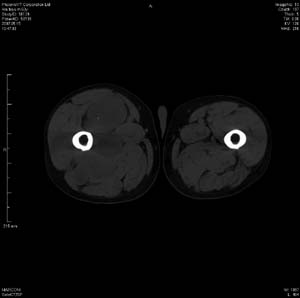

男 63岁 右大腿无痛性肿块11年,x片右大腿软组织肿块影,余无明显异常.ct值-13__239hu

右大腿股内侧股与收肌间隙间多发囊实性占位,界清.内示斑点状钙化.局部骨质无异常.肌肉推压移位表现.

考虑肌间隙病变.可有1,神经来源肿瘤.2,血管来源病变.3,淋巴来源肿瘤.4,脂肪来源肿瘤.5,滑膜来源肿瘤.结合病史只能考虑良性占位.建议增强或mri进一步分析.

同意,病史较长,病变周围分界清晰,考虑良性病变。病灶内有多发斑点状钙化,沿肌间隙生长,血管瘤或淋巴管瘤首先考虑。